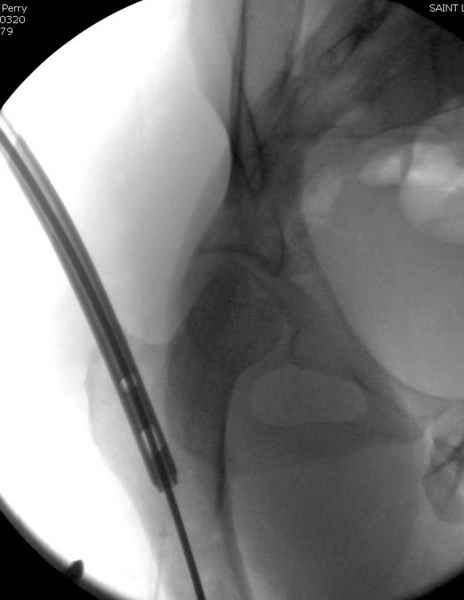

Второй случай тоже репозиция из малого доступа, больному 19 лет, множественные огнестрельные повреждениия конечностей, живота и черепа, правая конечность холодная, без пульсации. Ортопедический диагноз: огнестрельный перелом правого бедра. При срочной ангиографии повреждения сосудов не подтвердилось, конечность из-за ургентности состояния больного зафиксирована временным наружным фиксатором и больной оставлен на операционном столе для срочной лапаротомии хирургической службой.

Больной долго оставался нестабильным, только на 14 день удалось заменить на антеградный интромедуллярный штифт TFN (trochanteric femoral nail) SmithNephew. После неудачной попытки закрытой репозиции, несмотря на использование "joystick", проксимальный стержень от

наружного фиксатора, (перелом начал срастаться) репозицию провели из малого доступа, затем остальные этапы операции.

Случай был представлен из-за того, что больного оперировали после наружной фиксации и был риск инфекцирования через места проведения стержней (на снимках), прошло больше 3 месяцев, выписан из амбулаторной службы из-за отсутсвия надобности дальнейшего наблюдения.